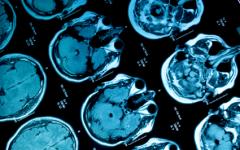

Образна диагностика в условията на COVID-19-пандемия

Негативната находка от конвенционалната рентгенография не отхвърля COVID-инфекция, както и може да е факт при леки форми на заболяване. Изразен задух, необясним с нормалния рентгенов образ, е показание за провеждане на компютърна томография (КТ) на белите дробове.